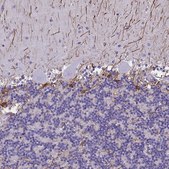

HPA056030

Anti-Glial Fibrillary Acidic Protein Antibody

Prestige Antibodies® Powered by Atlas Antibodies, rabbit polyclonal

immunohistochemistry: 1:2500-1:5000